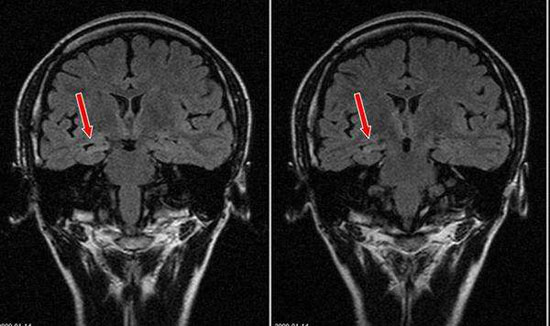

后来在网上查寻,看到中国医科大学航空总医院癫痫中心的介绍和治疗过的患者案例,便带孩子慕名来到医院。在神经外科癫痫专家门诊见到张光明教授,经过全面检查和综合评估,确认小红患有颞叶癫痫。张教授说:“在脑电图发现,患者左侧颞区放电多,而且大发作,很严重。”由于拖得时间久,病灶区有外延迹象,应及早手术切除病灶,防止迁延到右侧颞叶或其它重要功能区域,手术有一定难度。经过专家会诊和充分准备,2016年1月张光明教授为患者实施了左侧颞叶标准切除术。采用立体定向脑电图(SEEG)技术微创手术,手术历时7个小时,非常成功。手术后一年多了,小红康复得很好。这次来医院复查,患者说术后一年多没有发作过。